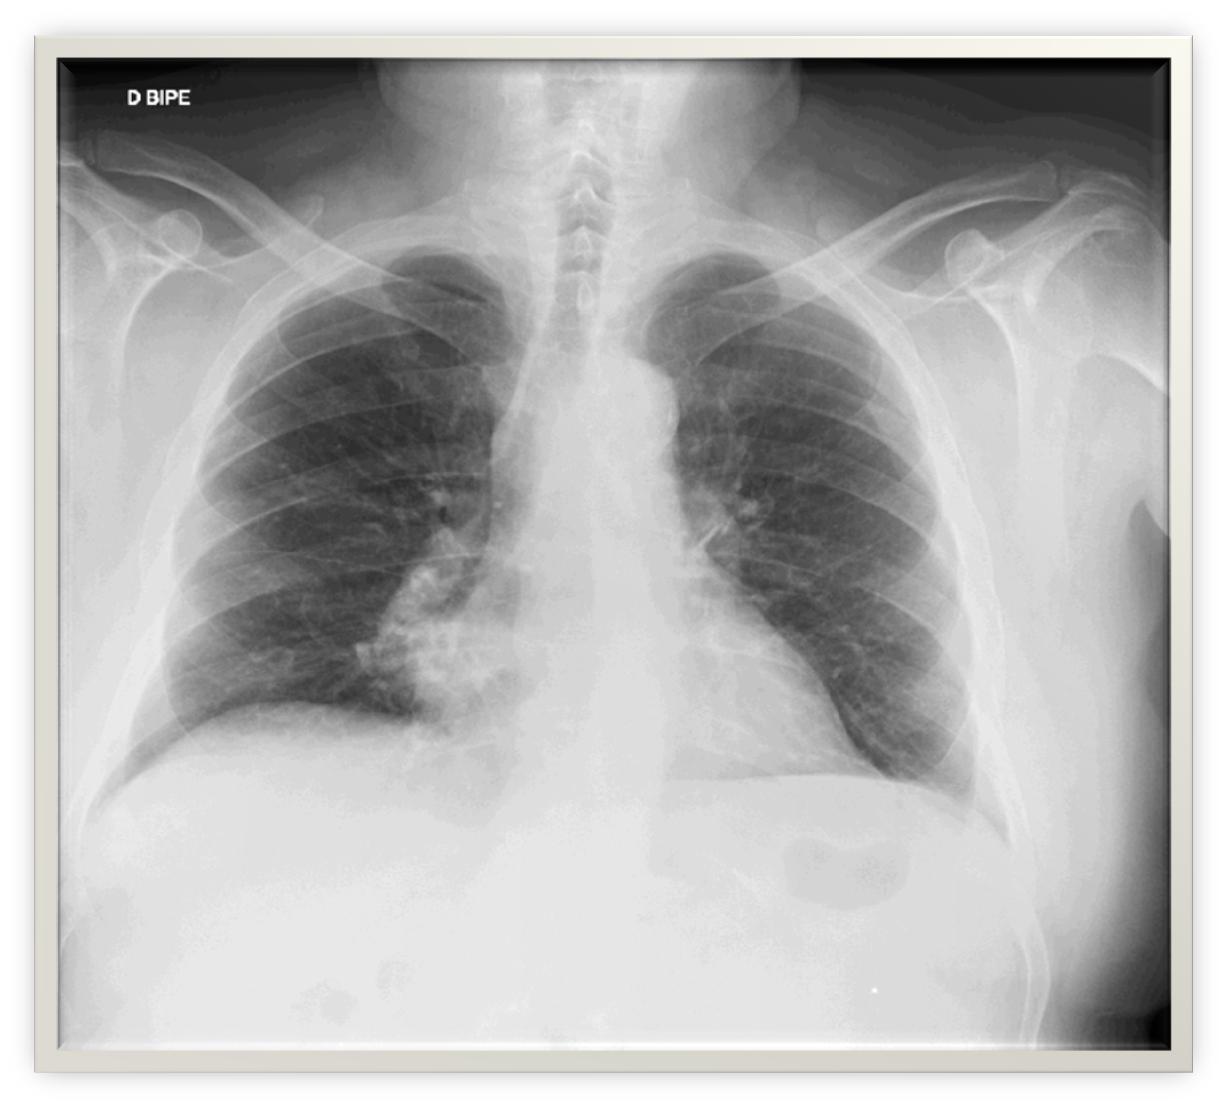

Rx tórax: